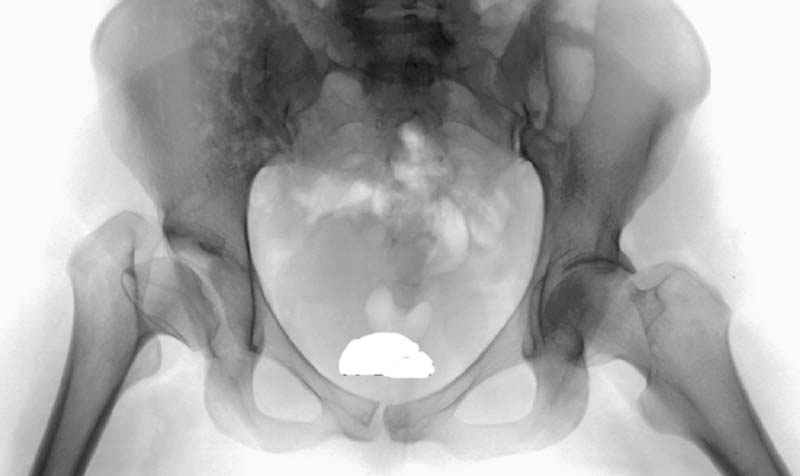

предоперационные снимки #8

предоперационные снимки #9

предоперационные снимки #10

№ 8-10 предоперационные снимки